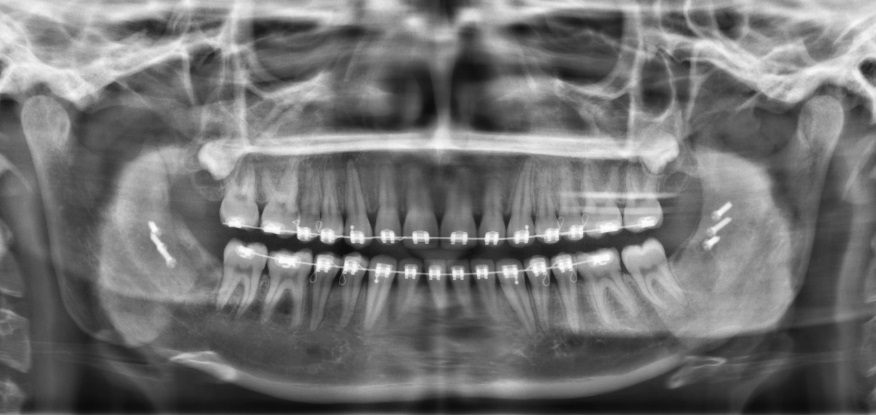

Vergrote overbeet door terugliggende onderkaak, onderkaak verlenging (BSSO advancement)

Röntgen beeld na operatie